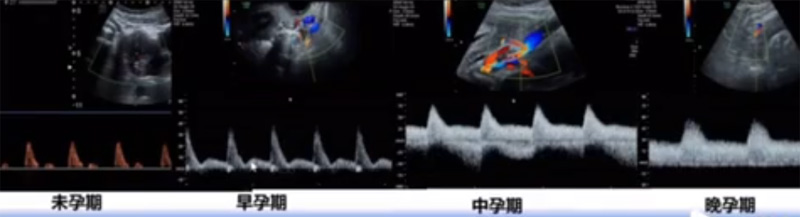

位于輸卵管的后下方,子宮兩側(cè)的后上方;借卵巢系膜與子宮闊韌帶后層相連。正常成人卵巢約4x3x2cm,跟睪丸的數(shù)值差不多,都是性器官,絕經(jīng)后卵巢萎縮變小、變硬。所以絕經(jīng)后婦女很難找到卵巢,主要功能:生殖和內(nèi)分泌功能分泌性激素。女性的第二性征。女性內(nèi)生殖器的血管分布,動脈有子宮動脈,卵巢動脈,陰道動脈,陰部內(nèi)動脈。靜脈它是與動脈伴行。重要了解的是子宮動脈,子宮動脈是髂內(nèi)動脈前干的重要分支,妊娠時(shí)候血流速度會增加的,為無創(chuàng)性檢查胎盤血管阻力的方法。未孕期頻譜為高阻力低舒張波形;正常妊娠時(shí)血流速度增加,血流阻力下降。